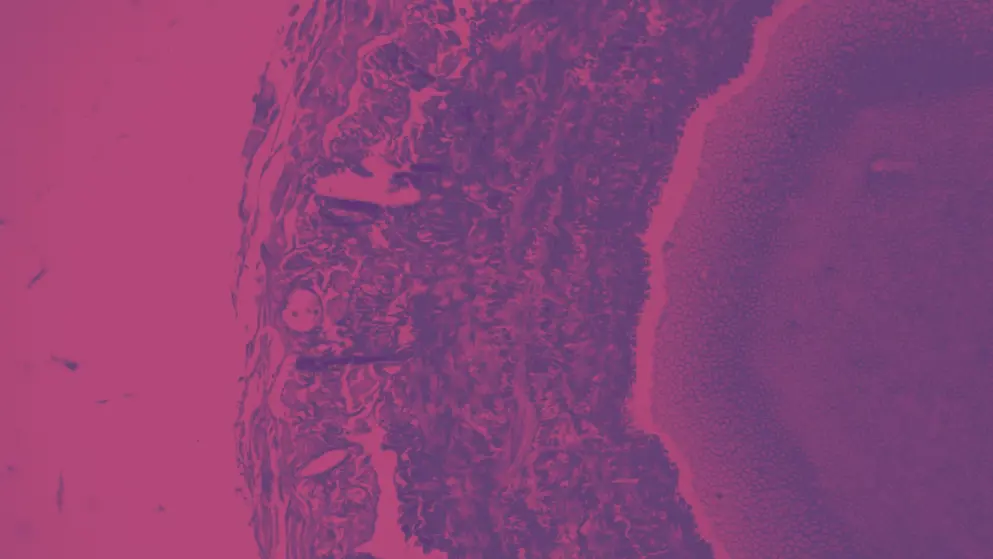

Finally, a revealed a strong association between Lp(a) levels and the presence and progression of coronary plaque measured on computed tomography angiography21.

Among 272 patients (average age 57 years, 42% women), each interquartile range (103 nmol/L) increase in Lp(a) levels was associated with a 1.17 percentage point higher percent atheroma volume at baseline and a 0.65 percentage point larger increase during follow-up averaging 10.2 years.